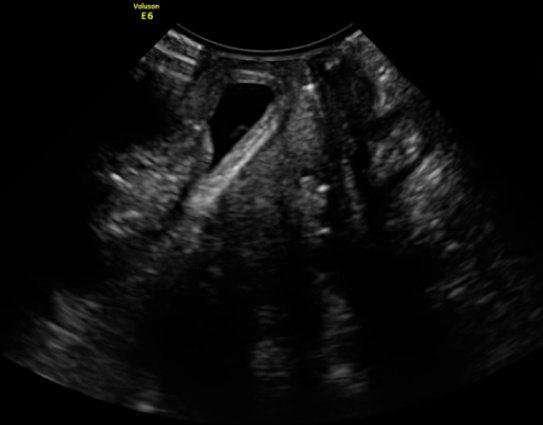

经过细致的盆底超声检查,医生确认王阿姨脱出来的“肿块”主要是膀胱的后壁,也就是所谓的Green III型膀胱脱垂;同时经过三维超声检查,王阿姨的耻骨直肠肌也没有明显的撕脱。根据超声结果,我院盆底疾病中心的医生为王阿姨定制了个性化的盆底治疗方案,现在王阿姨再也没有“肿块”的困扰了。

(静息状态)

(用力状态)